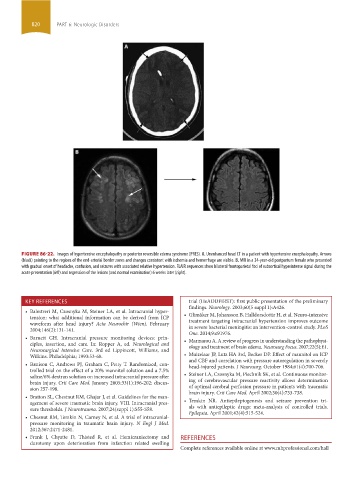

FIGURE 86-22. Images of hypertensive encephalopathy or posterior reversible edema syndrome (PRES). A. Unenhanced head CT in a patient with hypertensive encephalopathy. Arrows

(black) pointing to the regions of the end-arterial border zones and changes consistent with ischemia and hemorrhage are visible. B. MRI in a 34-year-old postpartum female who presented

with gradual onset of headache, confusion, and seizures with associated relative hypertension. FLAIR sequences show bilateral frontoparietal foci of subcortical hyperintense signal during the

acute presentation (left) and regression of the lesions (and normal examination) 6 weeks later (right).